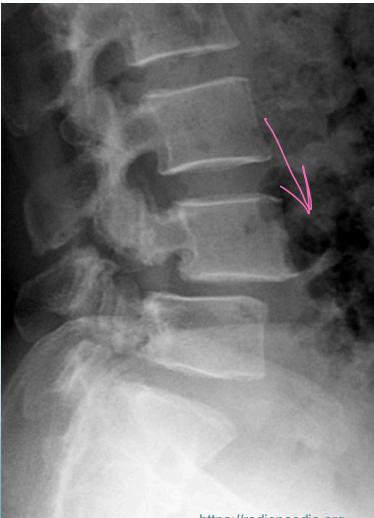

Diagnostic Imaging

- Lateral view: Shows vertebral slip

- Spondylolisthesis: Anterior vertebral displacement